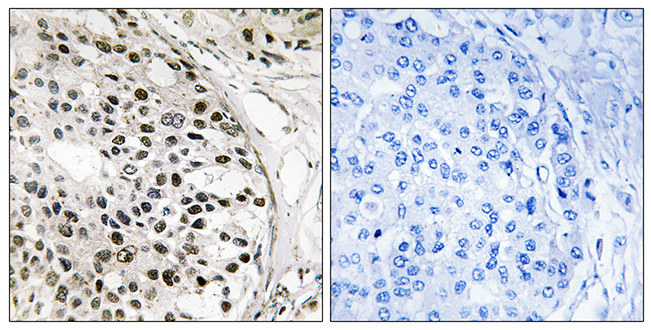

Anti-MNK1 AntibodyA97778

ApplicationsELISA, ImmunoHistoChemistry

ReactivityHuman, Mouse, Rat